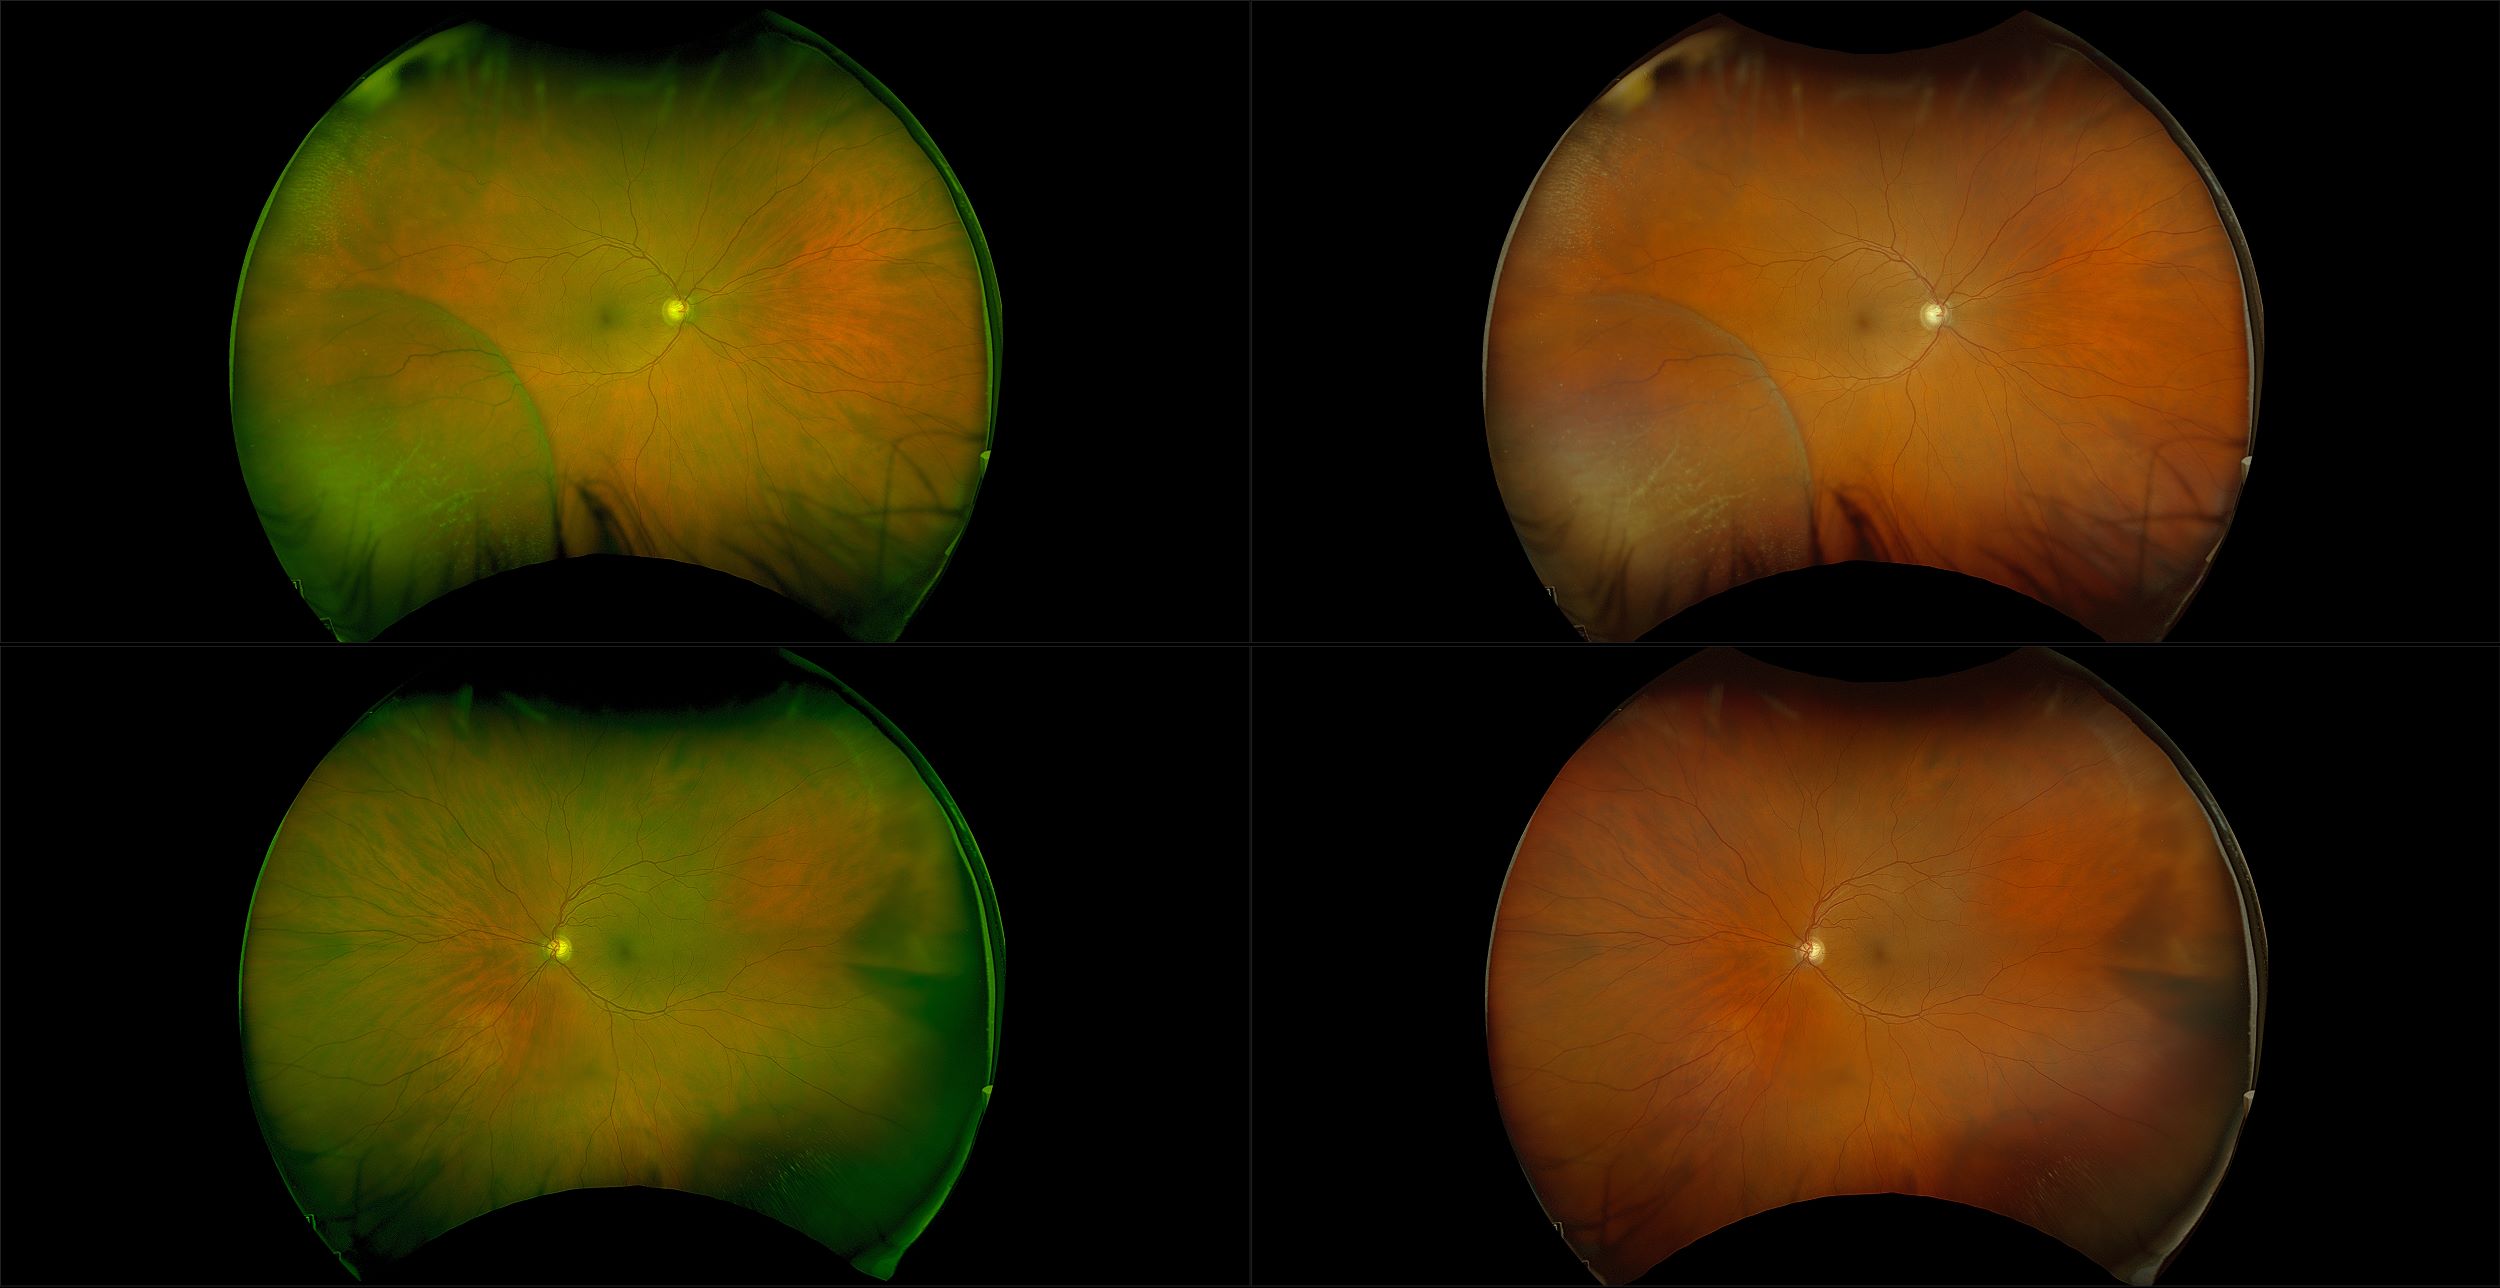

California - AMD, RG, AF

Age-related macular degeneration is found in two forms 1. Dry early form. 2. Wet (serous leakage or whole blood). Early dry form typically has drusen (usually around 63u) and RPE degeneration and only needs periodic follow-ups, intermediate dry form has large drusen (>125u) and RPE degeneration and proliferation which requires examinations every 3 to 6 months depending on the severity of the presentation.